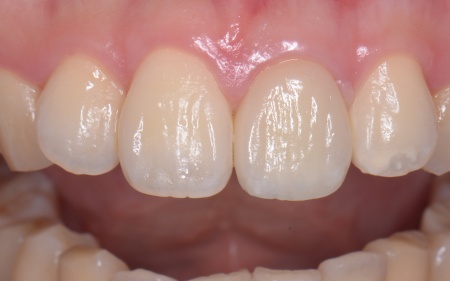

患者様は「できるだけ自分の歯のように自然な見た目にしてほしい」とご希望です。 そこで、白いグラスファイバーを用いた土台(ファイバーコア)に白い被せ物(ジルコニアセラミッククラウン)を装着する治療を提案し、同意いただきました。 ファイバーコアは光を通す素材のため自然な透明感があり、歯根への負担が少ないことが特徴です。 ジルコニアセラミッククラウンは、強度の高いジルコニアのフレームの上にセラミックを何層にも盛って焼き付けるレイヤリングを施した被せ物です。 治療初日は歯がないことで生じる不便さや見た目への影響に配慮し、その場で仮歯を作製して装着しました。 土台が完成したあとは歯科用顕微鏡のマイクロスコープで確認しながら、被せ物をスムーズに装着できるよう歯の形を丁寧に整えました。 その後、変形しにくいシリコン素材で精密な歯型を採取し、それをもとにジルコニアセラミッククラウンを作製しています。 |